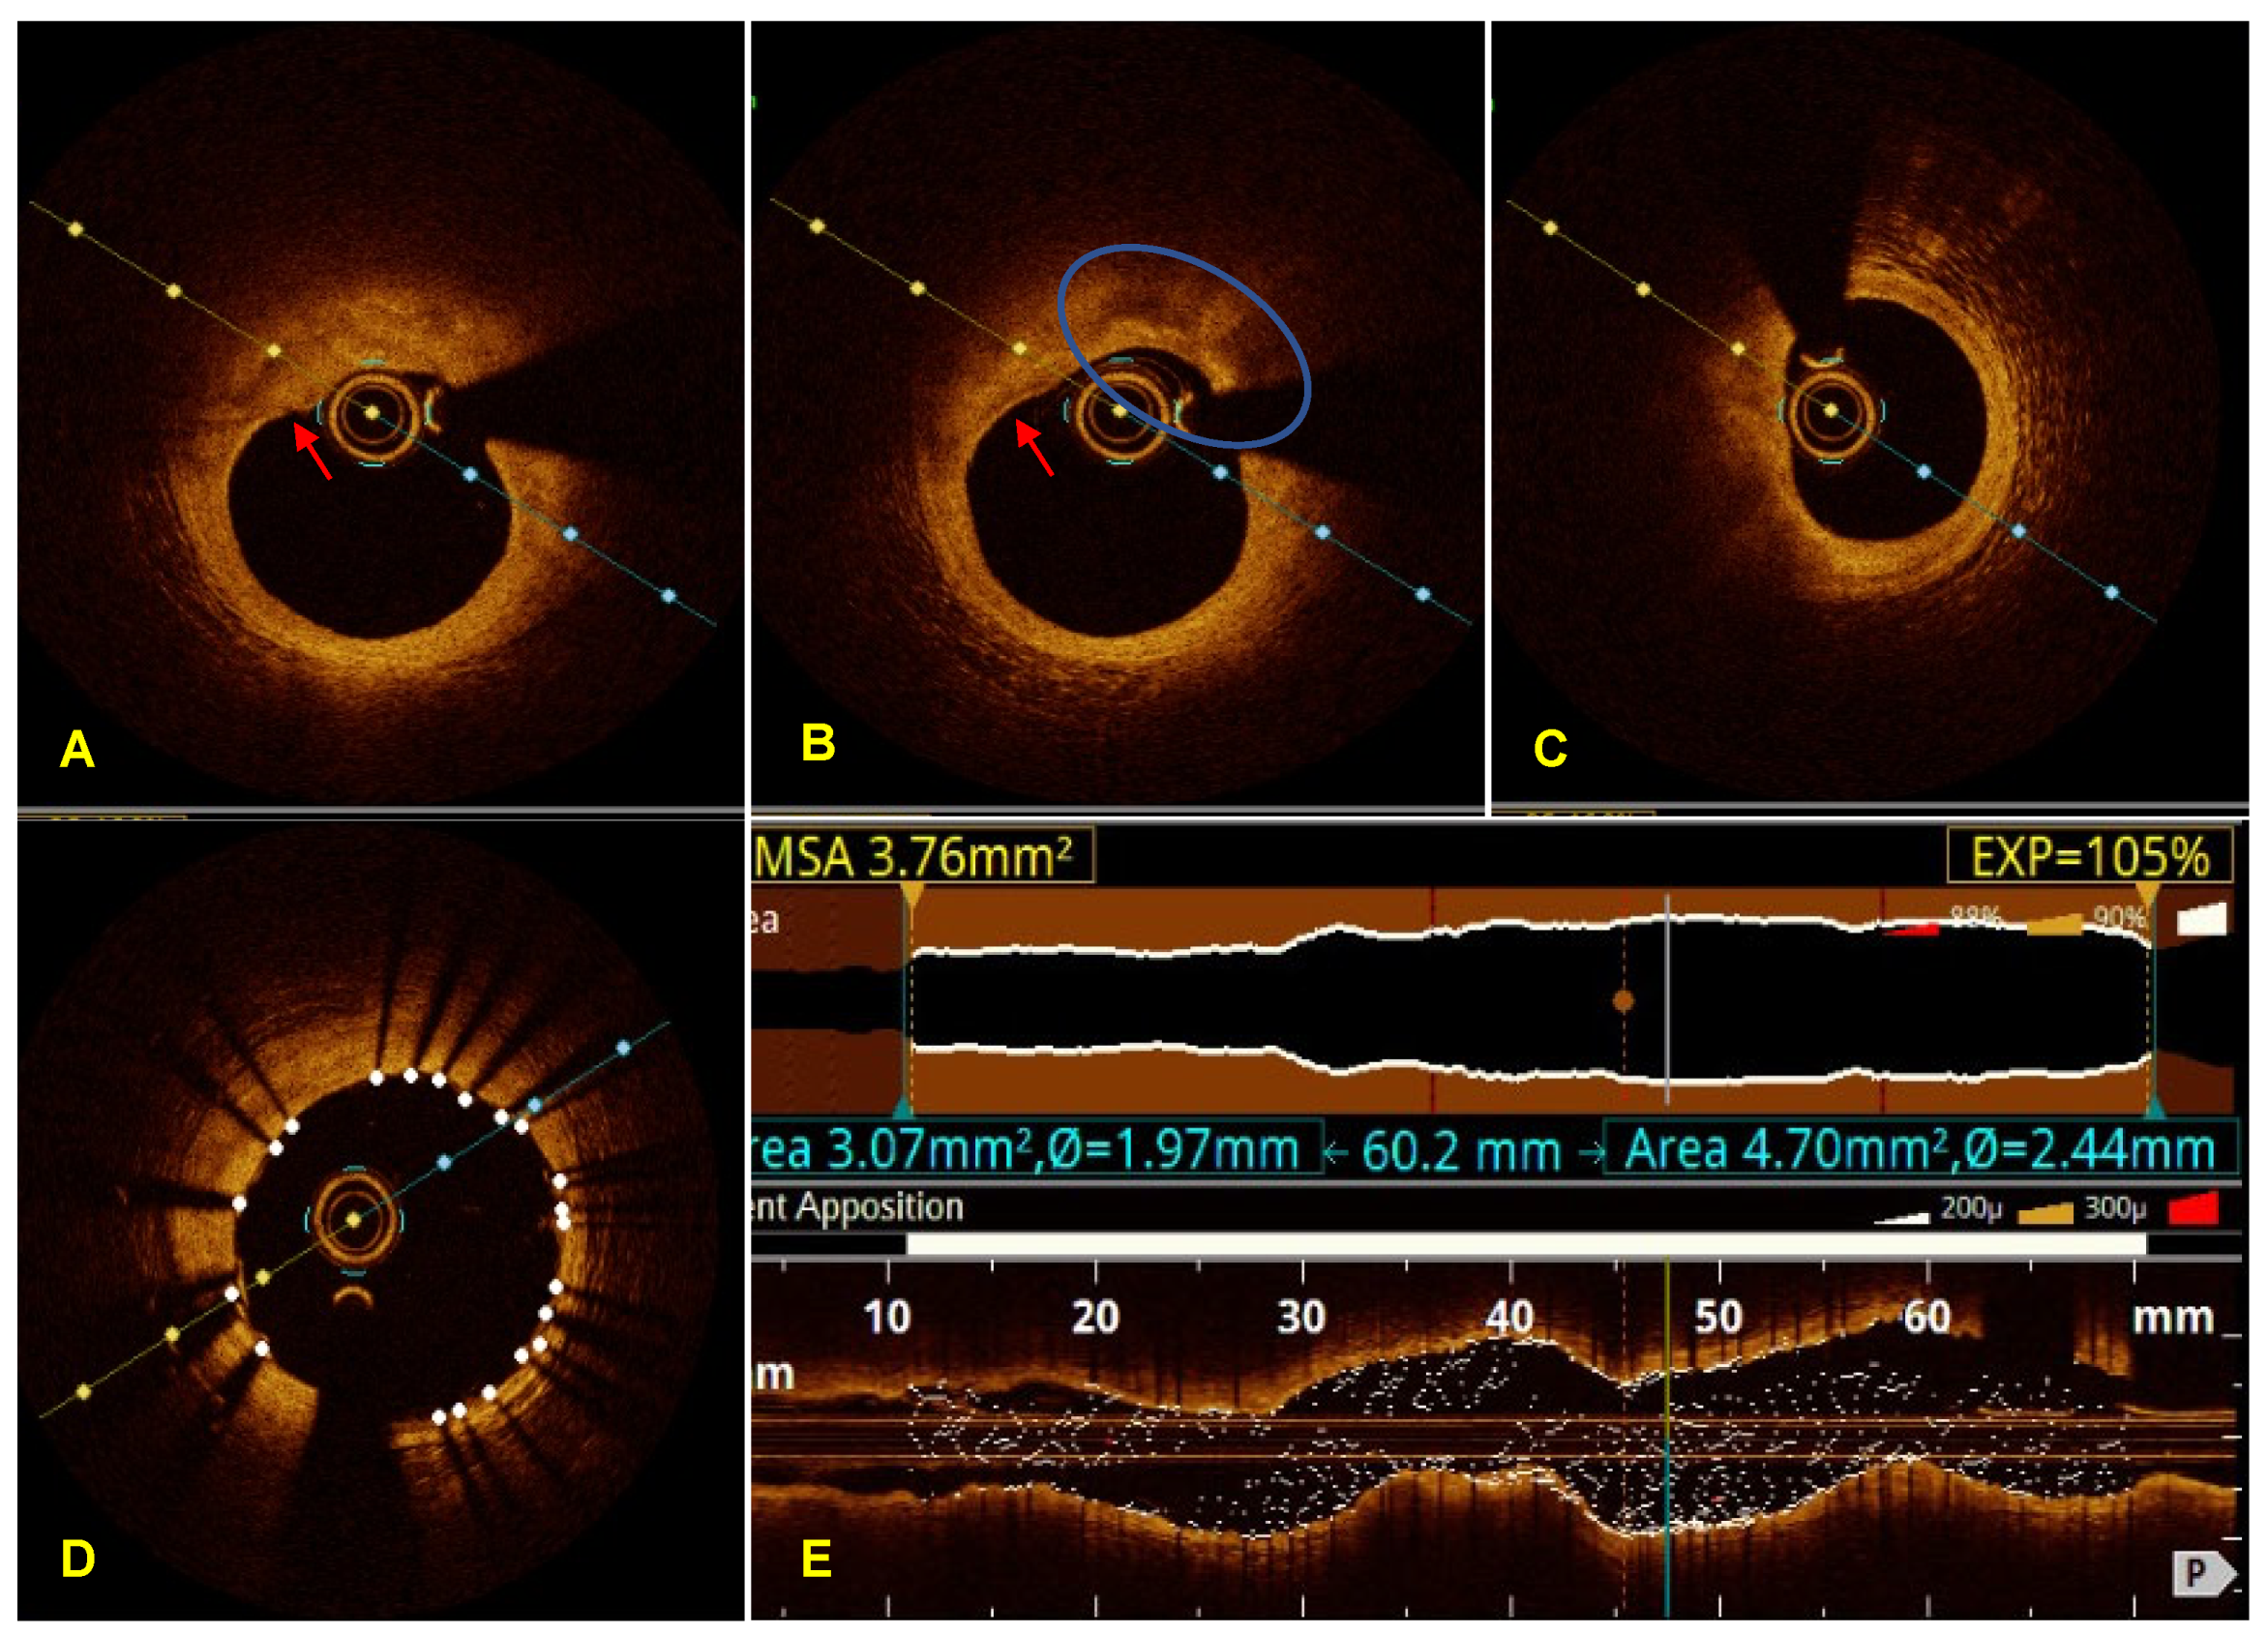

Acute Coronary Syndrome with Non-Obstructive Plaque on Angiography and Features of Vulnerable Plaque on Intracoronary Optical Coherence Tomography

3. Case Report